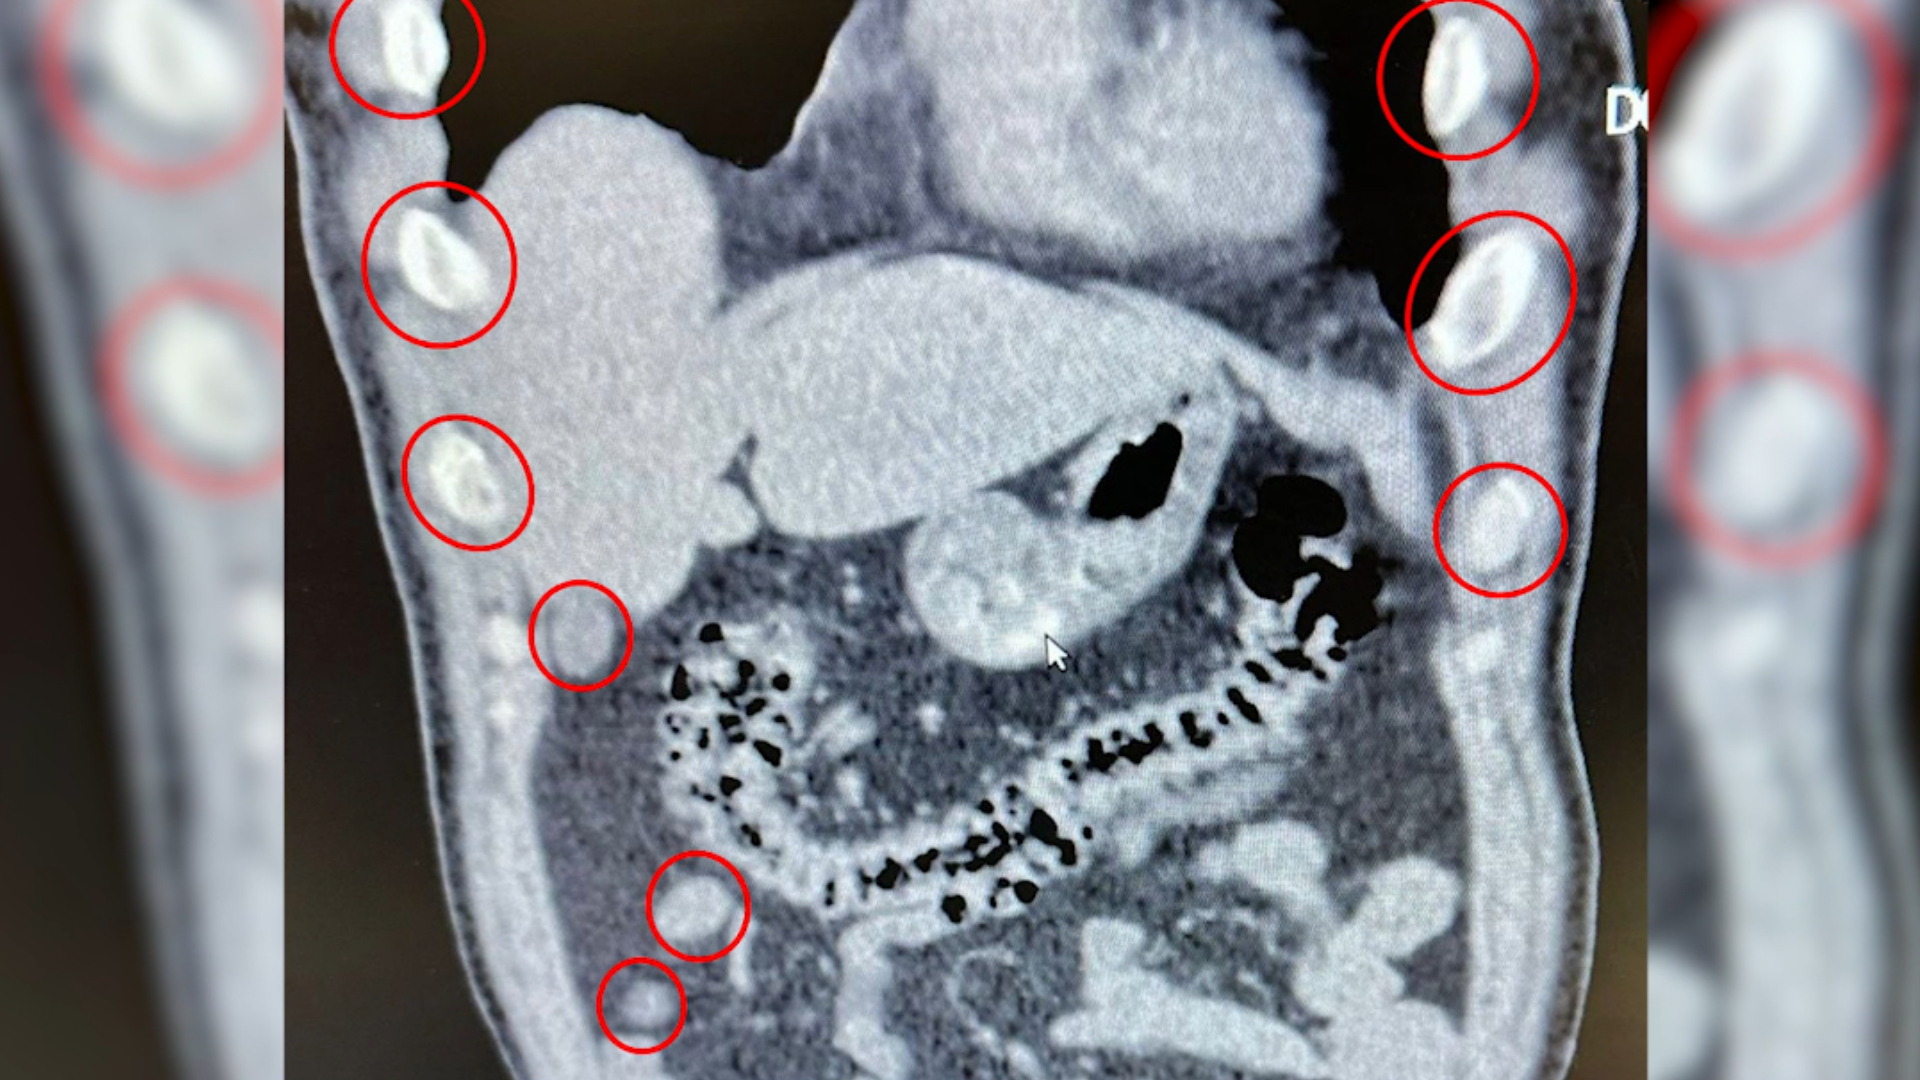

“Bitlis İl Emniyet Müdürlüğü Narkotik Suçlarla Mücadele Şube Müdürlüğümüzce uyuşturucu ile mücadele kapsamında yapılan çalışmalarda; Tatvan ilçemizde durdurulan bir otobüste yolcu olarak seyahat eden yabancı uyruklu 2 şahıs gözaltına alınmıştır. Gözaltına alınan ve Tatvan Devlet Hastanesine sevk edilen şahısların röntgen ve tomografi görüntülerinde mide ile bağırsaklarında çok sayıda yabancı cisim bulunduğu tespit edilmiştir.Yapılan tıbbi müdahale ile şahısların yuttuğu 136 kapsül olmak üzere toplam 1 kilo 48 gram Metamfetamin maddesi ele geçirilmiştir. Uyuşturucu Madde İmal ve Ticareti suçundan gözaltına alınan 2 şahıs çıkarıldığı adli mercilerce tutuklanmıştır. Hemşehrilerimizin huzuru ve güvenliği için uyuşturucu madde imalatı, kaçakçılığı ve kullanımına karşı yürütülen kararlı mücadelemiz devam edecektir.”